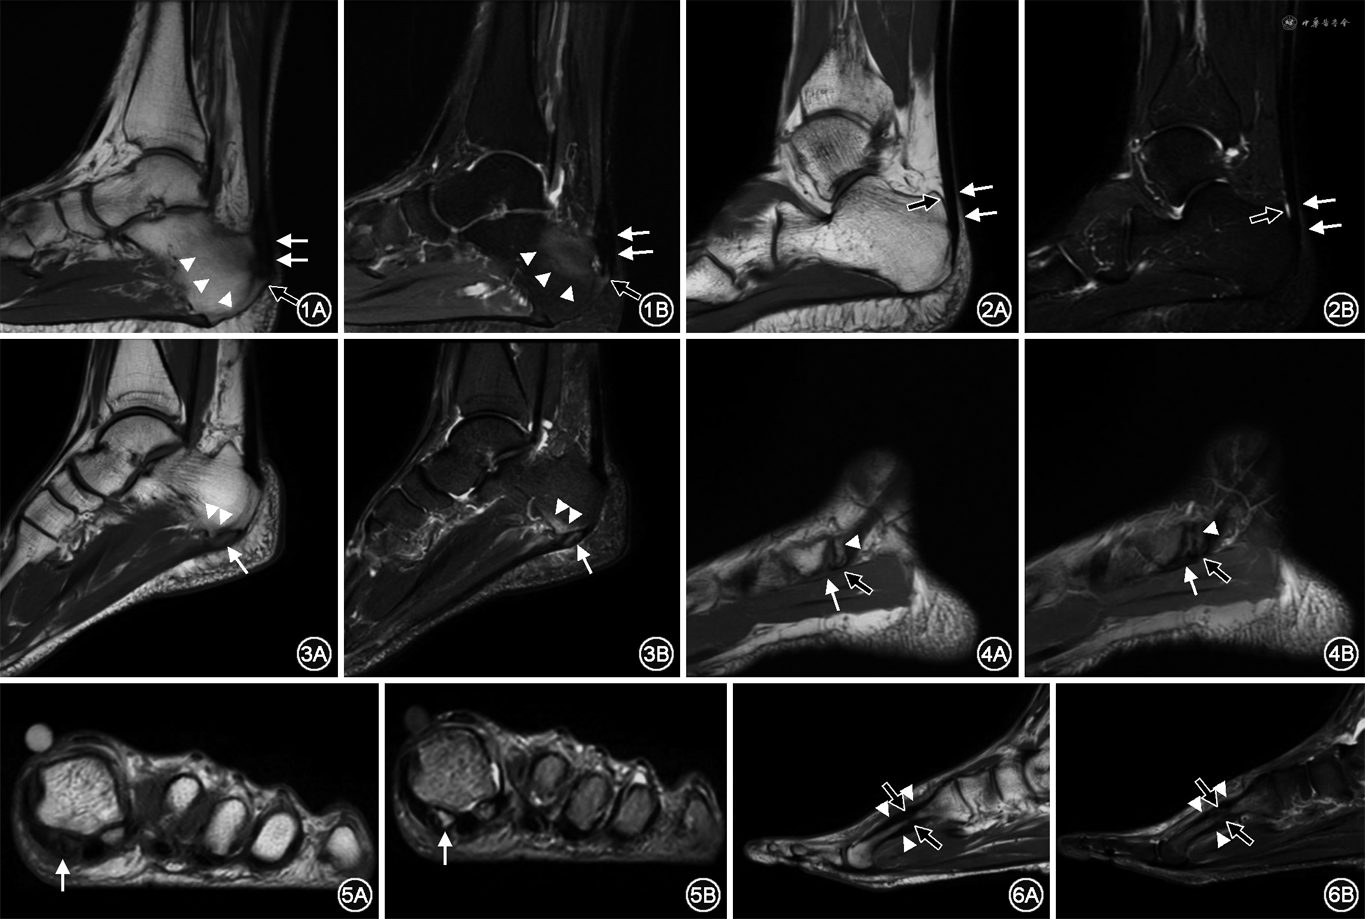

(1)肌腱和韧带损伤:①跟腱炎性病变共60侧,均表现有足痛症状,占35.71%(60/168),其中跟腱炎38侧,跟腱滑囊炎22侧(有6侧足伴发跖筋膜炎)。足痛程度分级FASS 1级54侧,2级6侧。跟腱炎在MRI表现为跟腱弥漫性或局限性增粗,T1加权像、STIR均可见跟腱内信号增高,跟骨止点可见骨刺形成、囊变,并可见跟骨骨髓水肿(图1)。跟腱滑囊炎表现为跟腱前或跟腱后滑囊积液,可伴周围脂肪间隙水肿,但跟腱本身无异常表现(图2);②跖筋膜炎:共40侧,均表现有足痛症状,占23.80%(40/168),其中有6侧同时伴发跟腱炎。足痛程度分级FASS 1级36侧,2级4侧。筋膜炎在MRI上表现为筋膜周围软组织水肿,或腱膜附着处的跟骨骨髓水肿(图3);③肌腱损伤:共14侧,均表现有足痛症状,占8.33%(14/168)。足痛程度分级FASS分级均为1级,其中胫骨后肌腱损伤6侧,腓骨前肌腱损伤2侧,腓骨后肌腱2侧,腓骨前、后肌腱同时损伤4侧。肌腱损伤在MRI上表现为损伤部分肌腱增粗、STIR信号增高,伴或不伴腱鞘增厚、积液,当周围增生或变异的骨质压迫肌腱时,表现为肌腱局限性受压表现,并见临近骨髓水肿(图4)。

(2)骨损伤:①第1跖骨籽骨损伤/籽骨炎:共10侧,均表现有足痛症状,占5.95%(10/168)。足痛程度分级FASS分级均为2级,在MRI上表现为T1WI不均匀低信号,STIR不均匀高信号(图5);②疲劳骨折:共4侧,均表现有足痛症状,占2.38%(4/168),其中3侧发生于第2跖骨,1侧发生于第3跖骨。足痛程度分级FASS分级均为2级,MRI上表现为病变部位髓腔内骨髓水肿,骨膜反应,并可见骨折线,病变部位周围软组织水肿(图6)。